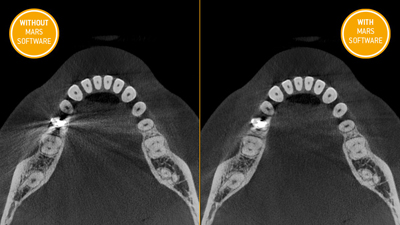

MARS-降低金屬散射技術金屬物成為3D影像的挑戰

特別是對於有金屬修復體的患者。透過MARS技術

重建演算,大幅降低金屬物的散射與陰影

大大提升3D影像的品質,提供牙科更準確的資訊